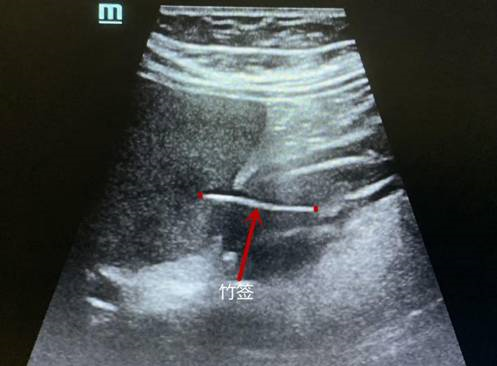

超声显示竹签位置(图片由清华长庚医院提供)

超声科谭庆亭医师反复检测,在患者的胃窦处发现了一个细细长长的异物,经张华斌主任当场会诊后,明确了诊断。此时,患者才努力地回想起,自己发病的前一天曾用竹签吃过包子。超声检查发现这根竹签已经刺破了胃壁,扎入了肝脏。“胃镜没发现是因为这根竹签的位置很特殊,它穿出了黏膜层,位于黏膜下。”超声科主任张华斌解释说。